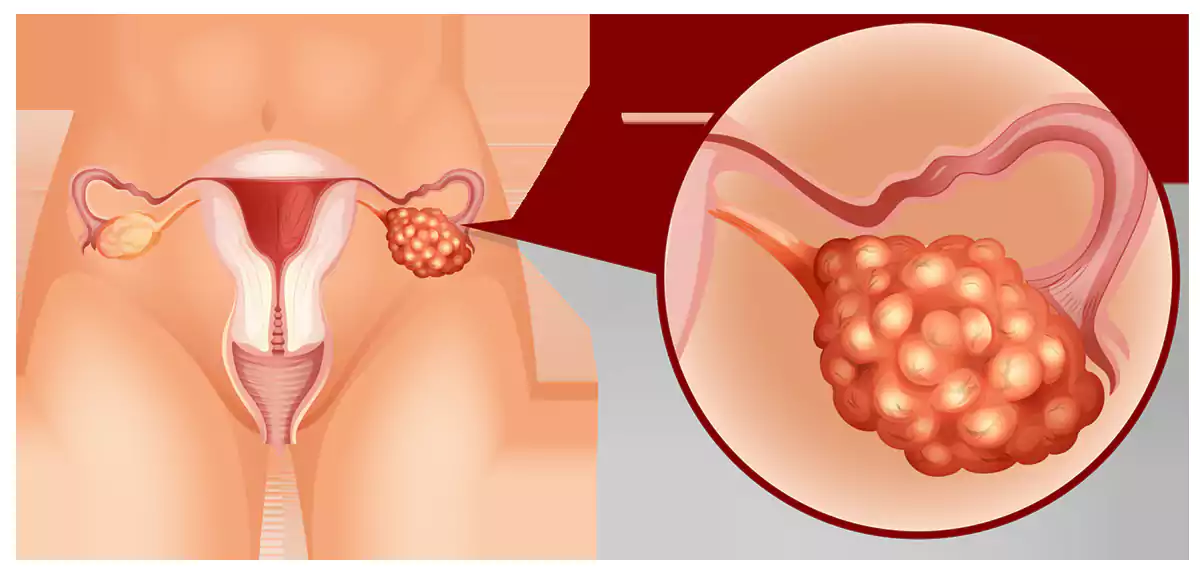

هیپرپلازی آندومتر

سرطان آندومتر